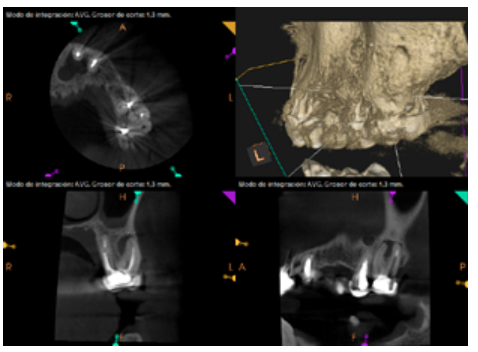

To confirm the endodontic origin and the size of the lesions, tomographic examinations were performed with a slice thickness of 75 microns using CBCT CS8100 (Carestream Dental™), in which radiolucent periapical lesions were observed at the level of 12, 11, 21 (with bicortical involvement), 25 and vestibular roots at 26 (Figures 4 to 8).

After the microsurgery was performed on 25, the patient had no symptoms and the control tomographies at 12 months (in 25) and at 18 months in the remaining teeth showed regeneration of pre-existing radiolucent periapical lesions on all treated teeth (Figures 13 to 16).

Radiological checks were carried out at 6, 12 and 18 months using CBCT, which showed the absence of symptoms and a reversal of the chronic infection, as well as progressivity and stability in apical bone regeneration. At the level of 21, periapical radiopacity was observed, without loss of volume, and an absence of invasion of the space preserved by the surrounding soft tissue. Although some authors have used plasma rich in growth factors (PRGF) associated with Bio-Oss™ and Bio-Gide™ in cases similar to ours, we obtained adequate results without using PRGF as an additional technique13.